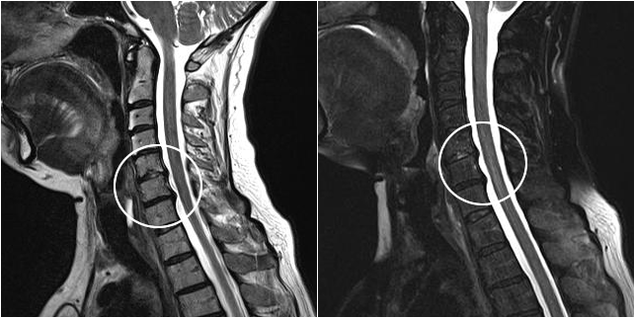

Metodele moderne de diagnostic includ RMN și CT, care fac posibilă examinarea cât mai precisă a proceselor de distrugere a cartilajului și a țesutului osos. De asemenea, folosind această tehnică este convenabil să se diagnosticheze herniile și alte defecte ale țesuturilor moi în apropierea sursei bolii.